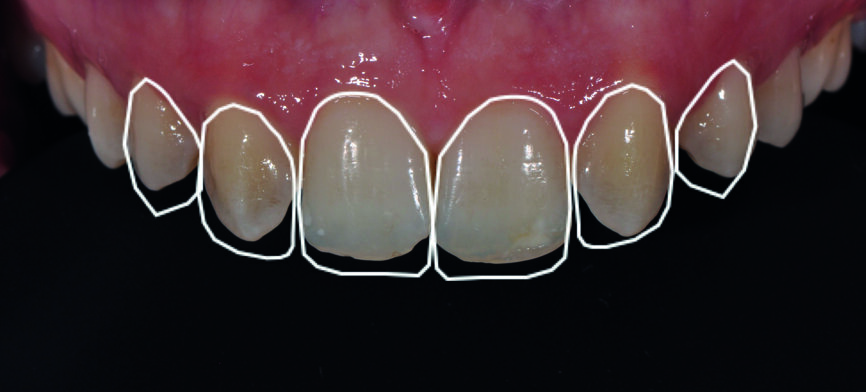

Fig. 1a : Sourire après la fermeture orthodontique.

Fig. 1b : Gros plan du sourire après la fermeture orthodontique. Il faut noter l’aspect jaunâtre des canines, les grandes embrasures des incisives et la ligne gingivale égalisée.